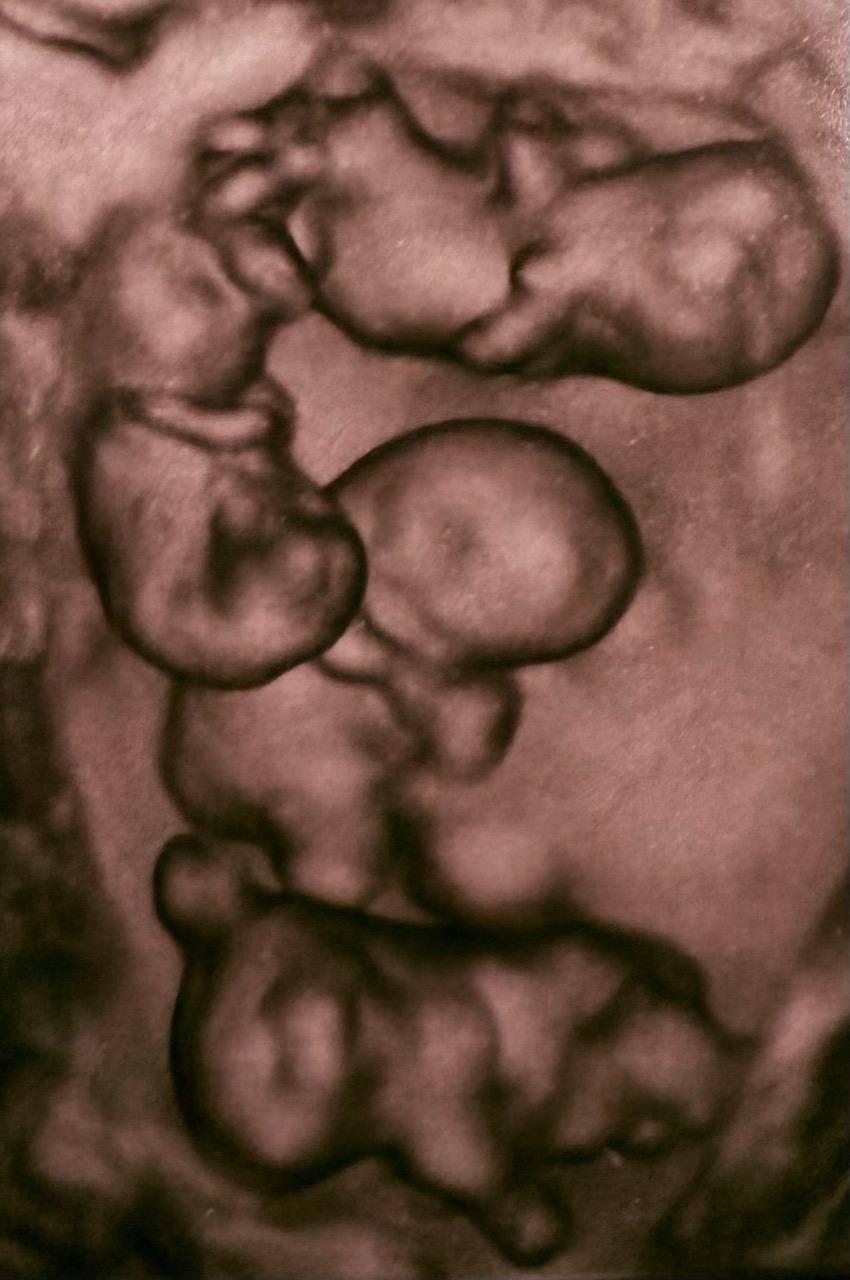

Однояйцевые близнецы

Своими наблюдениями в соцсетях поделился и профессор, главный врач роддома № 10 Евгений Михайлин, который консультировал пациентку: «Я эту пациентку консультировал как профессор-консультант в области гематологии-иммунологии репродукции. По расчетной статистике монохориальная — „однояйцевая“ четверня — 1 случай на 15,5 миллионов родов

В РФ не описано таких случаев! Получилось 32 недели, для четверни — это более чем прилично! Родились: 1. Девочка: 1400 г, 38 см; 2. Девочка: 1570 г, 41 см; 3. Девочка: 1640 г, 41 см; 4. Девочка: 1360 г, 37 см».

Отдельного внимания заслуживает и тот факт, что речь идет о монохориальной беременности. Это означает, что все четыре плода развивались с одной общей плацентой, что существенно усложняет течение беременности и требует постоянного медицинского контроля. В зависимости от условий развития эмбрионов такие беременности могут быть биамниотическими — когда у каждого плода есть своя амниотическая оболочка, или моноамниотическими — когда все развиваются в одной полости. Подобны случаи считаются крайне сложными и требуют высочайшего уровня подготовки врачей.